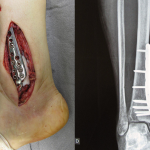

A tomografia evidencia tumor próximo à placa de crescimento, requerendo a ressecção da mesma, como margem oncológica (figura5). Como reconstruir este segmento em uma criança com sete anos de idade e evitar a discrepância dos membros inferiores? Nossa proposta foi realizar a ressecção do 1/3 distal da tíbia e reconstruir com a fíbula do mesmo lado, transferido a fíbula para a substituir a falha tibial. Nesta transferência levaríamos a fíbula vascularizada, com a placa fisária, artrodesando a sua epífise com o tálus e encavilhando o 1/3 proximal da fíbula no seguimento proximal da tíbia. Realizamos radiografias, arteriografia e planejamento para a execução (figuras 6.7 e 8).

A cirurgia de ressecção do tumor, englobando todo o terço distal da tíbia e a reconstrução deste segmento com o autotransplante da cartilagem de crescimento da fíbula para a tíbia são detalhados nas figuras 10 a 20.

A documentação radiográfica e acompanhamento da reabilitação da paciente, após a reconstrução, são ilustrados nas figuras 21 a 46.